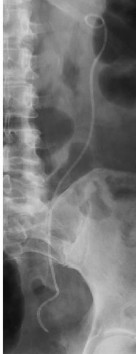

Vôi hóa ống thông niệu quản JJ

Các yếu tố khác nhau như nước tiểu quá bão hòa, mang thai, mang ống thông niệu quản thời gian dài… làm tăng nguy cơ vôi hóa bề mặt thông niệu quản [116].

Theo báo cáo của el-Faqih S.R. và cs (1991) [50] thì tỷ lệ vôi hóa ống thông niệu quản là 9,2% (đặt < 6 tuần), 47% (đặt 6 – 12 tuần) và khoảng 76,3% (đặt > 12 tuần). Theo báo cáo khác của tác giả Kawahara T. và cs (2012) [89] thì tỷ lệ vôi hóa ống thông niệu quản là 26,8% (< 6 tuần), 56,9% (6 -12 tuần) và khoảng 75,9% ( > 12 tuần). Sự vôi hóa có thể gặp ở đầu xa của ống thông nằm trong bàng quang, dọc theo chiều dài ống thông nằm trong niệu quản hoặc đầu gần của thông trong bể thận.

Hình 1.14. Ống thông niệu quản JJ vôi hóa trên phim hệ tiết niệu không chuẩn bị và nội soi bàng quang

(Nguồn: Aboutaleb HA, 2019) [15]